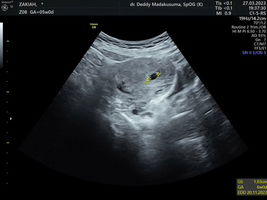

Diusia kehamilan 4 minggu apakah boleh berpuasa ramadhan

kalau saya disarankan obgyn tidak puasa dlu bund karena msh dalam pembentukan janin